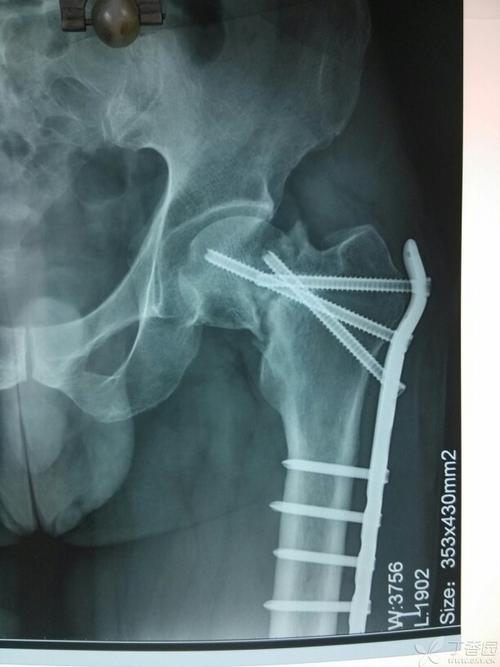

股骨颈骨折(头下型),有术后片!

股骨颈骨折内固定

股骨颈骨折空心钉固定